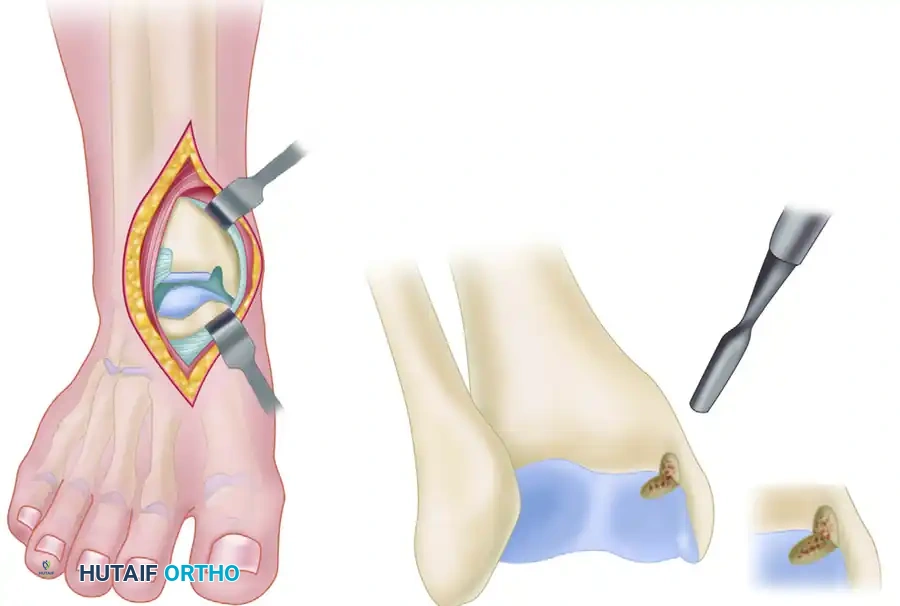

Arthroscopic Debridement and Microfracture

For lesions smaller than 1.5 cm², arthroscopic excision of the fragment, curettage of the necrotic base, and marrow stimulation (microfracture) is the gold standard.

- Positioning: Supine with a non-invasive ankle distractor.

- Portals: Standard anteromedial and anterolateral portals.

- Preparation: The loose fragment is excised. The sclerotic base of the crater is aggressively curetted until healthy, bleeding punctate bone is encountered.

- Microfracture: An arthroscopic awl is used to create holes 3-4 mm apart and 4-5 mm deep into the subchondral bone to release marrow elements (mesenchymal stem cells) that will form a fibrocartilage repair tissue (Type I cartilage).

Retrograde Percutaneous Drilling and Bone Grafting

For early lesions (intact cartilage but subchondral cystic changes/necrosis), retrograde drilling preserves the articular surface while stimulating healing. This is highly effective in young patients and those with open physes.

Arthroscopic retrograde drilling and bone grafting as described by Stone and Gould. (A) A guide pin is placed through the sinus tarsi using a modified ligament guide. (B) Graft material is compressed into the channel.

Surgical Steps:

1. Targeting: Under arthroscopic visualization, the intact articular cartilage is confirmed. A modified anterior cruciate ligament (ACL) drill guide is placed through the anterolateral portal, targeting the center of the lesion.

2. Drilling: A guide pin is advanced percutaneously from the sinus tarsi (for medial lesions) or the medial talar neck (for lateral lesions) into the subchondral cyst, stopping just short of the articular cartilage.

3. Fluoroscopic Confirmation: Intraoperative C-arm fluoroscopy confirms the trajectory and depth.

4. Decompression and Grafting: The tract is over-drilled. The cystic contents are curetted. To prevent articular collapse, the void is backfilled. Options include cancellous autograft, surgical-grade calcium sulfate, or bone marrow aspirate concentrate (BMAC) harvested from the iliac crest.

Retrograde drilling of an osteochondral lesion. After confirming intact cartilage, the subchondral lesion is drilled in a retrograde fashion and grafted.